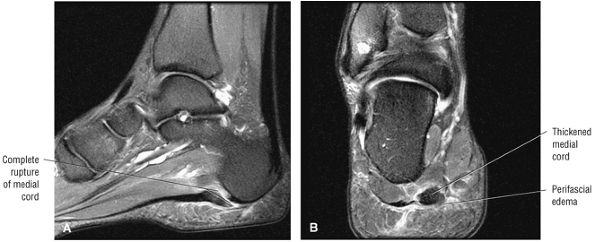

FIGURE 5.137 ● Normal MR appearance of the spring ligament complex. (A) Axial PD image demonstrates the lateral and intermediate calcaneonavicular ligaments originating from the notch between the anterior and middle articular facets of the calcaneus. The lateral calcaneonavicular ligament inserts on the navicular beak. (B) Axial PD image a few slices superior demonstrates the superomedial calcaneonavicular ligament deep to the posterior tibial tendon as it passes along the lateral aspect of the talar head toward its attachment to the dorsal aspect of the navicular tubercle. (C) Coronal T1-weighted image at the level of the talar head demonstrates the superomedial calcaneonavicular ligament deep to the posterior tibial tendon along the lateral aspect of the talar head.

|

![]() |

FIGURE 5.138 ● Pathologic appearances of the superomedial calcaneonavicular ligament. (A) Coronal FS PD image with fat saturation demonstrates a thickened and mildly edematous superomedial calcaneonavicular ligament in a patient who also had posterior tibial tendon strain. (B) Axial FS PD image with fat saturation demonstrates a thickened and edematous superomedial calcaneonavicular ligament in the setting of a partial posterior tibial tendon tear. (C) Axial PD image demonstrates a heterogeneous and irregular superomedial calcaneonavicular ligament in the setting of posterior tibial tendinosis and pes planus.